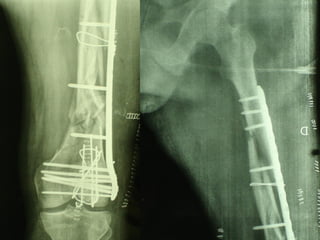

Dal Gennaio 2000 al Febbraio 2006 abbiamo trattato 167 fratture chiuse  con placca percutanea  in 164 pazienti :  27 lesioni diafisarie di gamba, 12 piloni tibiali ,  11 fratture prossimali di tibia, 36 fratture sovracondiloidee di femore, 17 fratture diafisarie di femore, 43 fratture metaepifisarie prossimali di omero, 21 diafisarie d’omero.  156 guarigioni 8 fallimenti

Dal Gennaio 2000 al Dicembre 2005 27 placche LISS di femore

INDICAZIONI COMUNI Fratture sovracondiloidee Fratture intercondiliodee Fratture diafisarie distali PARTICOLARI Fratture con grave osteoporosi Fratture periprotesiche

VANTAGGI CHIRURGIA MININVASIVA Mini Open Inserimento della placca sottocutaneo per scivolamento Viti percutanee Preservazione dei tessuti molli Ridotto danno vascolare Rapida ripresa funzionale